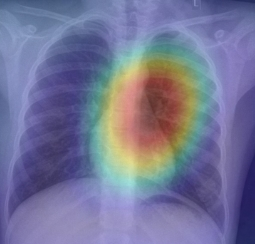

DenseNet121 • Transfer Learning • GradCAM

Deep learning for chest X-ray pathology detection with interpretability via GradCAM.